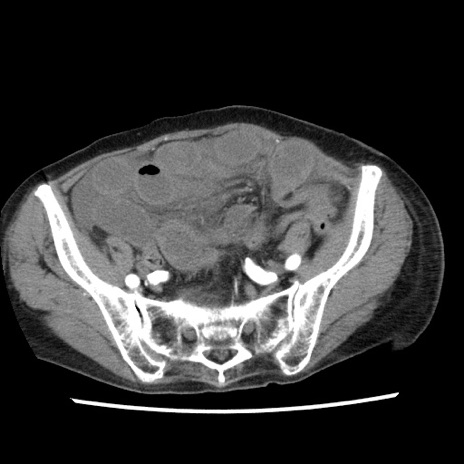

症例1(横断像)

【症例】80歳代女性

【主訴】腹痛

【現病歴】8時間前から腹痛あり来院。

【既往歴】糖尿病、脂質異常症、子宮体癌にて子宮全摘術

【身体所見】意識清明・会話良好だが腹痛で苦悶様、全腹部にわたって反跳痛と圧痛あり

【データ】WBC 13600、CRP 0.14、LDH 224、CK 90